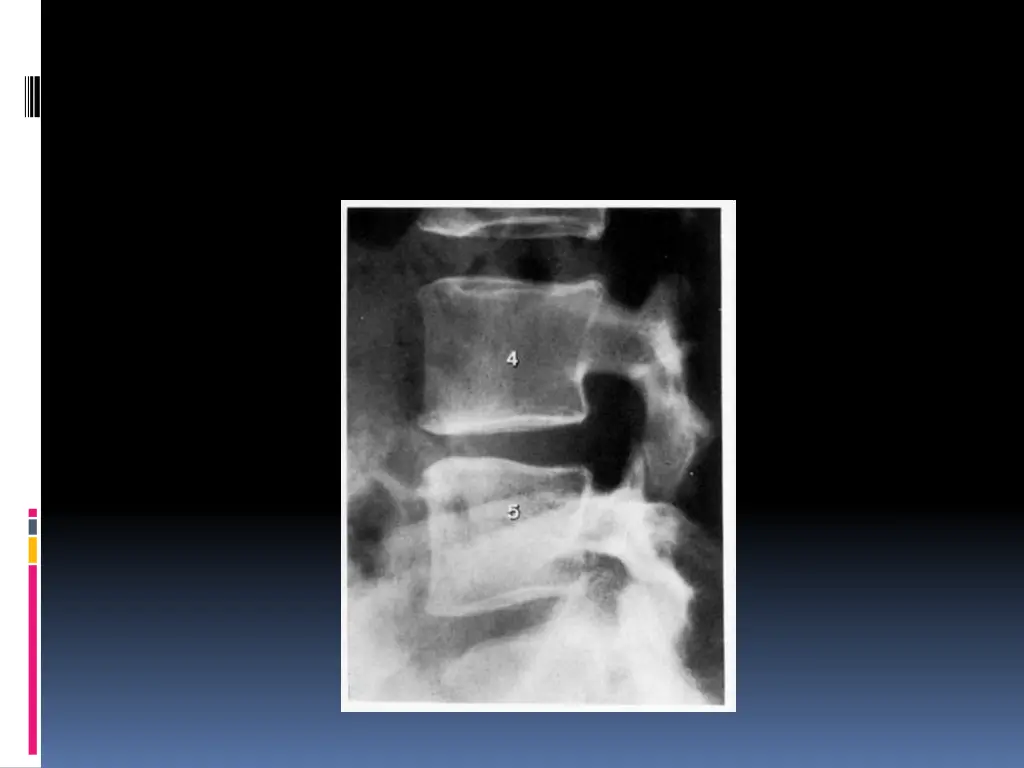

Diffrents types de HD A : Protrusion discale B : HD sous ligamentaire C : HD ext rioris e D : HD exclue ou libre

Examens complmentaires Interrogatoire + examen clinique=== diagnostic de sciatique commune Minimum : Un bilan inflammatoire Radiographies standards Incidences : -bassin de face debout (articulations sacro-iliaques,articulations coxo- f morales et du sacrum -rachis lombaire face + profil (statique, anomalie transitionnelle, qualit de l os,analyse des disques dont la hauteur peut tre diminu e, d veloppement arthrosique

SCANNER: Visualise la hernie, sa situation, son importance et la surface utile du canal rachidien. Coupes millim triques sus et sous-jacentes l espace discal v rifient l ventualit d une migration et son importance L IRM: Si la TDM ne d c le pas la hernie Si r cidive apr s CHX My lographie ou saccoradiculographie EMG